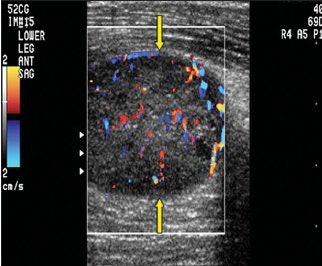

| Schwannoma in a 75-year-old man. Above, color Doppler ultrasonography of the lower anterior leg shows a well-defined oval mass (arrows) with peripheral and central color flow signals, suggesting a hypervascular tumor. Below, neurofibroma in an 84-year-old man. Color Doppler ultrasonography of the right thigh shows a well-defined mass (arrows) with peripheral and central hypervascularity. |

Overall, ultrasound exams did not lead to statistically significant results for making the differential diagnosis, the authors stated. The internal echogenicity was hypoechoic in 100% of the schwannomas and 100% also showed posterior acoustic enhancement. Likewise, 96.2% of the neurofibromas were hypoechoic and 96.2% showed posterior acoustic enhancement. On color Doppler, all showed hypervascular changes. Additional results are shown below.

These results dovetailed with the traditionally held notion that ultrasonography cannot distinguish between the two entities because both are "well-defined solid hypoechoic soft-tissue masses with posterior acoustic enhancement," the authors wrote (Journal of Ultrasound in Medicine, February 2008, Vol. 27:2, pp. 161-166).